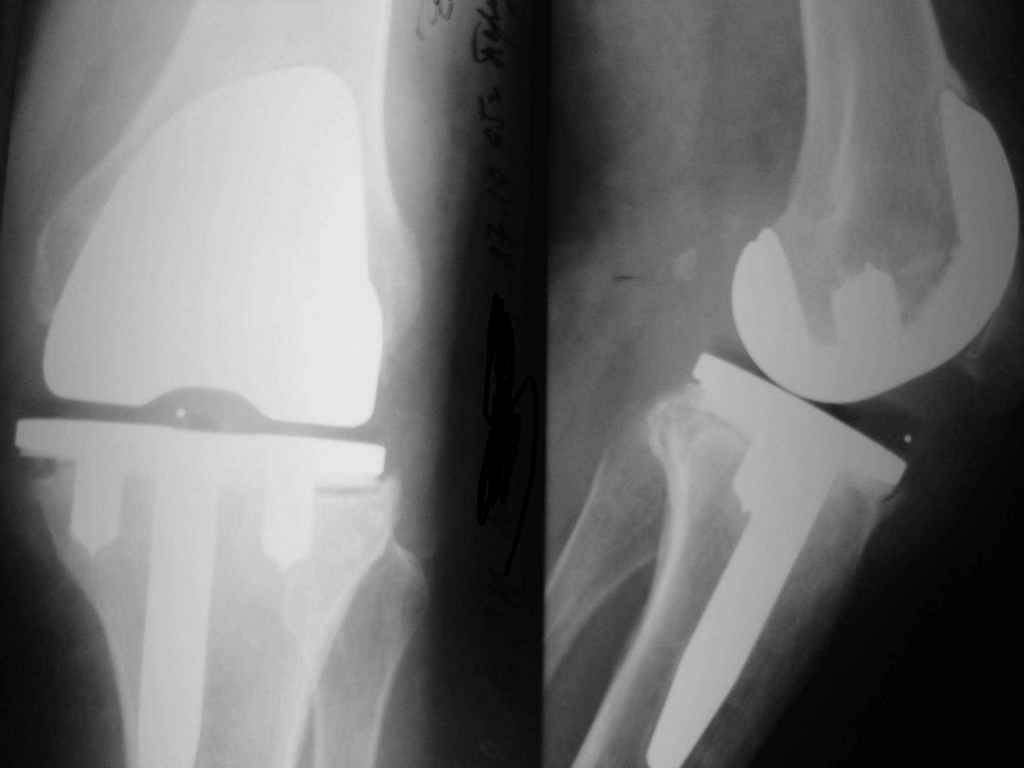

Уважаемые коллеги. Пациентка 65 лет соматически сохранна 6,5 месяцев назад выполнено замещениеколенного сустава интегральным эндопротезом Фримана Самуэльссона - цемент, по поводу ДОА. Послеоперационное течение с длительным субфебрилитетом. Местно без особенностей и выписана домой на 28 сутки с обьемом движений в колене 90 град. с частичной опорой. Дома отмечала субфебрильную лихорадку. Живет в небольшом поселке далеко от цивилизации. Контрольный осмотр в 3 месяца особых клинических проблем лечащий врач не нашел. Однако рентгенологически отмечены зоны остеопороза вокруг компонентов, на которые не обратил внимание. С 4 месяца отметила ухудшение - отек в колене, ограничение движений и боль. Лечилась у местного врача-хирурга (нестероиды и местно мазилки) - без эффекта. Обратилась только в 6,5 мес. Движения в суставе 20 град, отечность колена, выпот по УЗИ. Боль неопределенная, ходит с тростью. Лихорадки нет, в ан крови СОЭ 36 остальное норма, острофазовые тесты СРР повышен вдвое = 12 (при норме 6) Ревмотест - норма..Пункция - посев - роста не дает. Пробовали артроскопию - артрофиброз. Трудности осмотра из-законтрактуры и спаек. Рентгенограммы в динамике - в приложении (динамика с ухудшением). Вопросы:1. Инфекция? или остеопения местная? 2. Ревизия или подождать и полечить остеотропами? Благодарю заранее за любой совет. А Рыков. Хабаровск.

Показание к ревизии - нестабильность протеза (его компонентов) В приведённом Вами случае на Рг очевидная зона резорбции вокруг тибиального компонента следствие этого его нестабильность. Наиболее вероятна вялотекущая инфекция( судя по показателям крови и клиническим проявлениям: отек, боль, выпот и как следствие - ограничение функции)